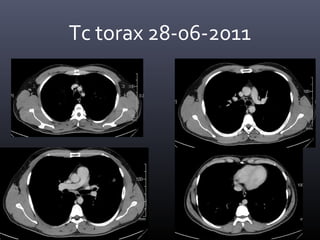

Tc torax 28-06-2011

• CONCLUSION TOMOGRAFICA:

• Nódulo pulmonar cavitado en el segmento 4 izquierdo con

afección de parénquima adyacente, lo cual como primera

posibilidad corresponde a Tuberculosis y diagnostico

diferencial de Coccidiodiomicosis.